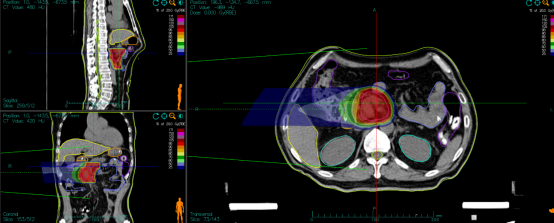

病例展示二:前列腺癌

XXX,男,64岁,主诉:间断性会阴部疼痛10月,确诊为前列腺癌7月。盆腔核磁:前列腺偏左侧异常强化占位,多考虑前列腺Ca,并左侧精囊腺受侵可能,盆腔左侧略大淋巴结。前列腺癌标志物提示:TPSA 88.67 ng/ml,FPSA 3.84 ng/ml。病检:(前列腺穿刺组织左侧)前列腺腺泡腺癌,Gleason评分4+3=7分;(前列腺穿刺组织右侧)Gleason评分3+3=6分。诊断:1、前列腺恶性肿瘤 双侧 腺泡腺癌Gleason评分4+3 =7分 cT3bN0M0 III期 KPS评分:80分。治疗方案:醋酸戈舍瑞林缓释植入剂 10.8mg 皮下注射、比卡鲁胺胶囊 50mg 口服 1次/天”全身治疗,并行前列腺癌碳离子治疗,剂量:57.6 Gy(RBE)/16 Fx。